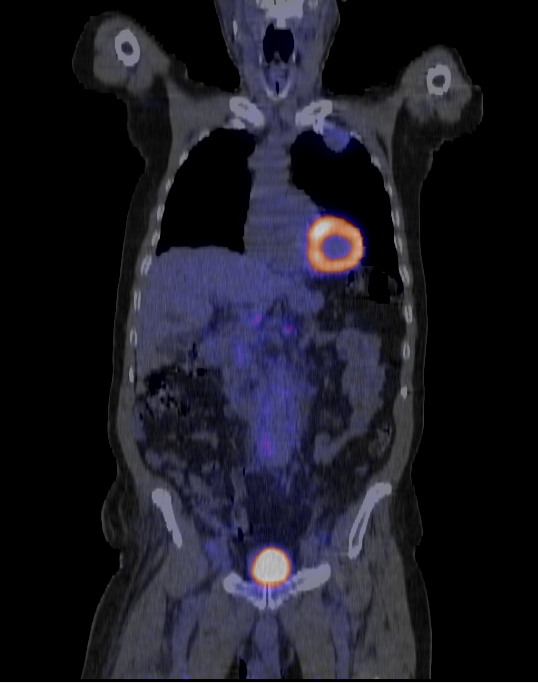

The result should look like this: